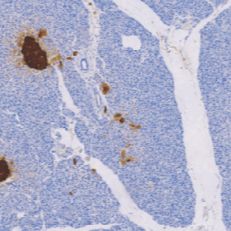

ChromograninA(CgA)鼠抗人嗜铬素A单克隆抗体

CgA是人类肾上腺髓质中含量最高的一种可溶性酸性蛋白,厂泛存在于神经元及其神经内分泌细胞和肿瘤细胞中,主要用于神经内分泌肿瘤如: 垂体肿瘤、胰岛细胞瘤、嗜铬细胞瘤、甲状腺髓样癌、类癌等的诊断

- 阳性部位:胞质

- 适用组织:石蜡切片

- 预处理:热修复